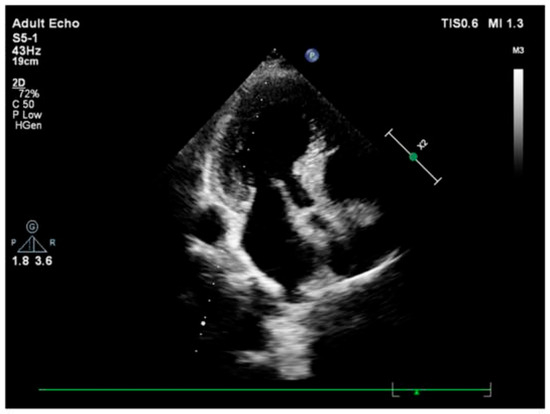

3.2. Imaging and Hemodynamic Observations

- Çağatay, B.; Yalçin, F.; Kıraç, A.; Küçükler, N.; Abraham, M.R. The Science Behind Stress: From Theory to Clinic, Is Basal Septal Hypertrophy the Missing Link between Hypertension and Takotsubo Cardiomyopathy? Stresses 2024, 4, 330–341. [Google Scholar] [CrossRef]

- Seyani, C.; Adam, R.; Gant, D.; Shambrook, J.; Flett, A. A Dynamic Variant of Takotsubo Cardiomyopathy Mimicking Apical Hypertrophic Cardiomyopathy: A Case Report. Eur. Heart J. Case Rep. 2025, 9, ytae432. [Google Scholar] [CrossRef] [PubMed]

- Yalçin, F.; Çağatay, B.; Küçükler, N.; Abraham, T.P. Geomeric and Functional Aspects in Hypertension and Takotsubo: Importance of Basal Septal Hypertrophy. Eur. J. Prev. Cardiol. 2023, 30, 1996–1997. [Google Scholar] [CrossRef]

- Merli, E.; Sutcliffe, S.; Gori, M.; Sutherland, G. Tako-Tsubo Cardiomyopathy: New Insights into the Possible Underlying Pathophysiology. Eur. J. Echocardiogr. 2006, 7, 53–61. [Google Scholar] [CrossRef]

- Abuarqoub, A.; Garis, R.; Shaaban, H.; Khaddash, I.; Shamoon, F. Takotsubo Cardiomyopathy with Basal Hypertrophy and Outflow Obstruction in a Patient with Bowel Ischemia. Int. J. Crit. Illn. Inj. Sci. 2018, 8, 44–47. [Google Scholar] [CrossRef]

- Yalçin, F.; Muderrisoǧlu, H. Tako-Tsubo Cardiomyopathy May Be Associated with Cardiac Geometric Features as Observed in Hypertensive Heart Disease. Int. J. Cardiol. 2009, 135, 251–252. [Google Scholar] [CrossRef]